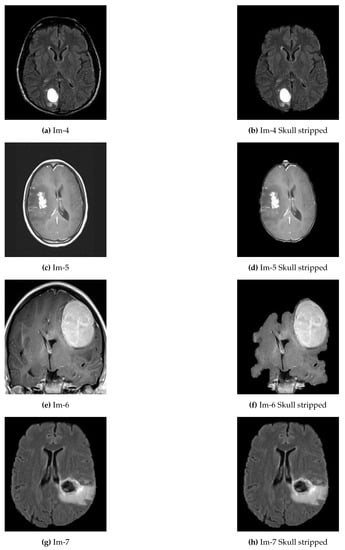

In the proposed approach, we applied thresholding and morphological operation for preprocessing (see Algorithm 1). Since the MRI images in the local dataset are images with three color channels, it was changed into a grayscale image before the preprocessing. Otsu’s thresholding technique was employed to determine the threshold between the background and the tissue regions. By thresholding, the largest binary object extracts the brain and removes the skull and other tags from the image. Some examples of skull removal algorithm are presented in Figure 2.

Figure 2.

Examples of original abnormal brain tumor images before and after skull removed. (a,c,e,g) represent original brain images with skull; (b,d,f,h) represent the skull removed original brain images.

The first experimental result was the skull stripped brain images as indicated in Figure 2 where Figure 2a,c,e,g were the original brain images of size and Figure 2b,d,f,h were the skull stripped brain images. Then, as presented in Equation (1), we generated 32 average intensities for each skull stripped brain images and selected the five top average intensities for each image and used as potential initial seed points for region growing algorithm as indicated in Figure 3a,c,e,g. Using the five selected initial seed points for each image, we generated five different ROIs and compared against the respective GT and selected the best ROI as presented in Figure 3b,d,f,h.